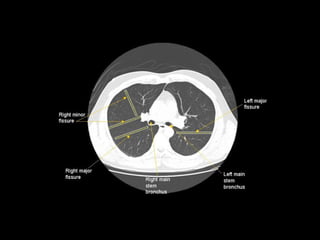

Radiographers use medical imaging equipment like X-rays and MRIs to produce images of patients' internal structures and organs. They are responsible for positioning patients, operating scanning machines, and ensuring quality images. Radiographers must have strong attention to detail, excellent communication skills, and the ability to work well under pressure to accurately capture anatomical features and diagnose any abnormalities.